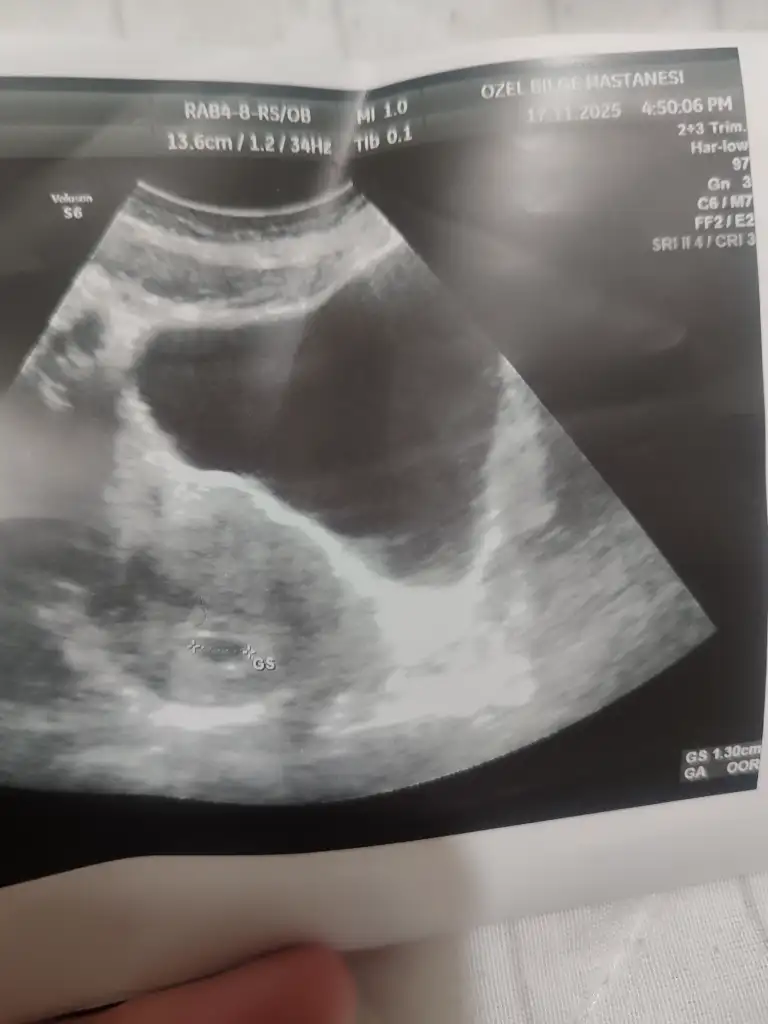

Cok normal canım 5+1 de gittim kese anca göründü küçüktü 4+5 uyumluydu 6+1 de tekrar gittim 1.30 olmuştu kese içi boş gibi demişti doktor yolk saç varla yok arası secilemiyordu vajinal de baktı aynıydı cok erken daha kese küçük dedi haftaya cagırdı 7+1 de gittiğimde hem bebeği hem kalp atısı gördüm cok şükür ogunde 6+6 ile uyumluydu bebiş ultrason görüntülerini ekliyorum fikir olsun için rahat etsinHanımlar 5+2 de doktora gittim kese 15mm idi ama bebeğe dair bişey gözükmedi normal mi doktorum 25mmye kadar görünür dedi biraz korktum açıkçası

Uyy minacık dah büyük hallerinide göreceği daha ayy çok sabırsızlanıyorummCok normal canım 5+1 de gittim kese anca göründü küçüktü 4+5 uyumluydu 6+1 de tekrar gittim 1.30 olmuştu kese içi boş gibi demişti doktor yolk saç varla yok arası secilemiyordu vajinal de baktı aynıydı cok erken daha kese küçük dedi haftaya cagırdı 7+1 de gittiğimde hem bebeği hem kalp atısı gördüm cok şükür ogunde 6+6 ile uyumluydu bebiş ultrason görüntülerini ekliyorum fikir olsun için rahat etsin

İlk foto 7+1 de diğer 2 foto 6+1 den karından ve vajinalden